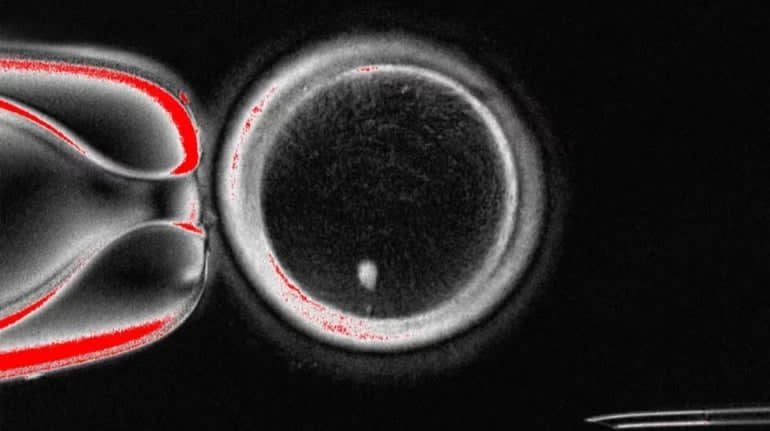

Яйцеклітина. Фото: theguardian.com

Науковцям вдалося створити функціональні людські яйцеклітини із частин клітин шкіри. Цей метод може в майбутньому відкрити нові способи боротьби з безпліддям для жінок, які через хвороби не мають власних яйцеклітин, та дозволити мати генетично споріднених дітей одностатевим парам.

Щоб створити яйцеклітину, науковці використовували ядра клітин шкіри – вони містять значну частину генетичної інформації. Згодом їх пересаджували в донорську яйцеклітину, в якій не було власного ядра.

Дослідники використовували метод, завдяки якому в 1996 році вчені клонували вівцю Доллі. Однак у випадку нової роботи її автори створили яйцеклітину, яка була генетичною копією одного з потенційних батьків. Це допомогло отримати яйцеклітини, які мали спільну ДНК із людиною, шкіру якої використовували.

Найбільшим викликом дослідників було переконатися, що запліднена яйцеклітина має правильну кількість хромосом. Для цього вони розробили метод видалення зайвих хромосом, який імітував природний поділ клітин.

Попри ці досягнення менше ніж 9% яйцеклітин дожили до стадії, яка відповідає п’ятому-шостому дню після запліднення. У випадку ЕКО в цей час ембріони зазвичай переносять у матку.

Автори роботи вважають, що метод може стати новою віхою у розробці способів боротьби з безпліддям. Однак для цього потрібні додаткові дослідження.